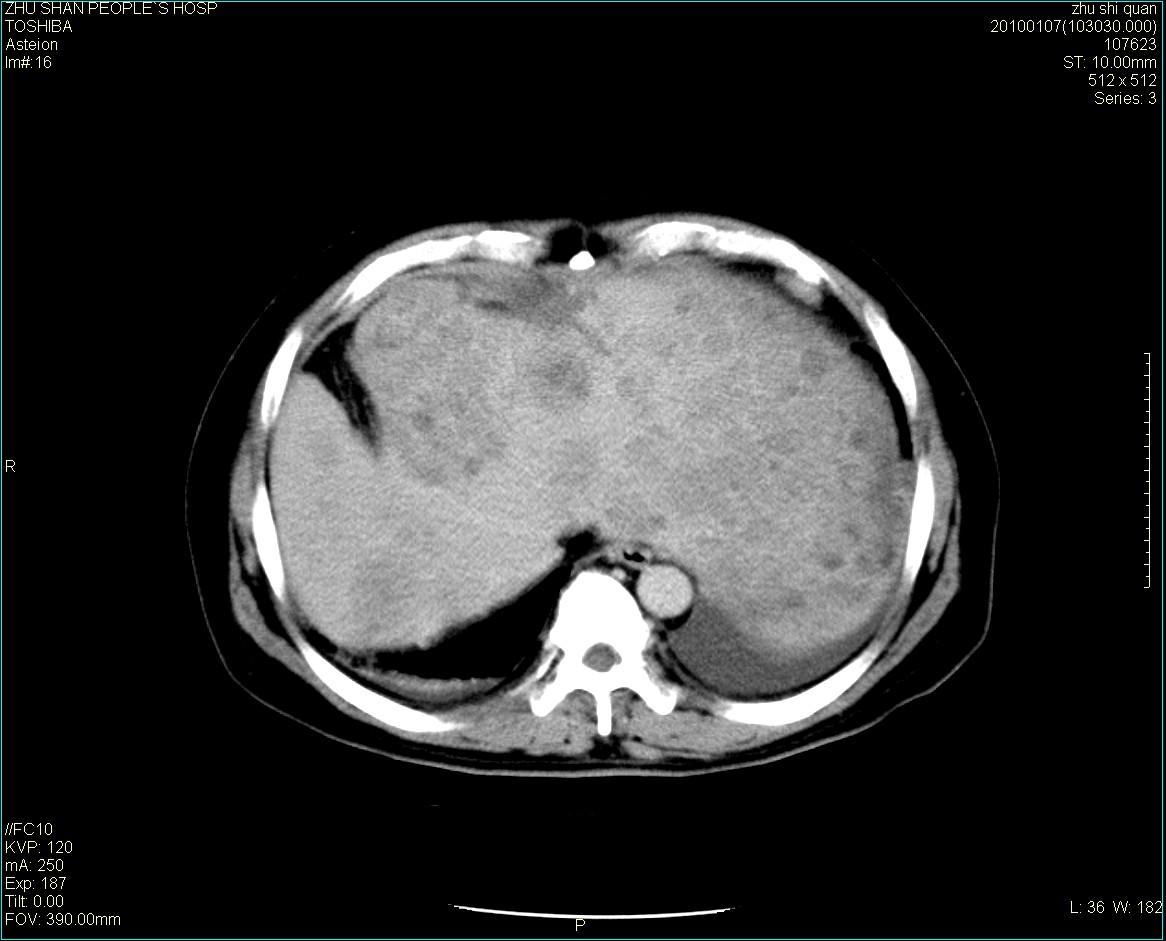

男性病人 肝ca两次术后,今日复查。

多发转移

肝、脾多发转移灶,胸腔积液

多发转移灶

1)肝癌并多发性转移。2)双侧胸腔积液(以左侧为甚)伴左下部分肺萎陷。

肝癌术后复发,考虑肝、脾多发转移。

肝癌术后复发,肝内、脾脏、腹膜后及腹膜多发转移,腹水,双侧胸腔积液(以左侧为甚)伴左下膨胀不全。

肝、脾多发转移灶,胸腔积液。

肝癌术后复发,肝内、脾脏、腹膜后及腹膜多发淋巴结转移,腹水,双侧胸腔积液。